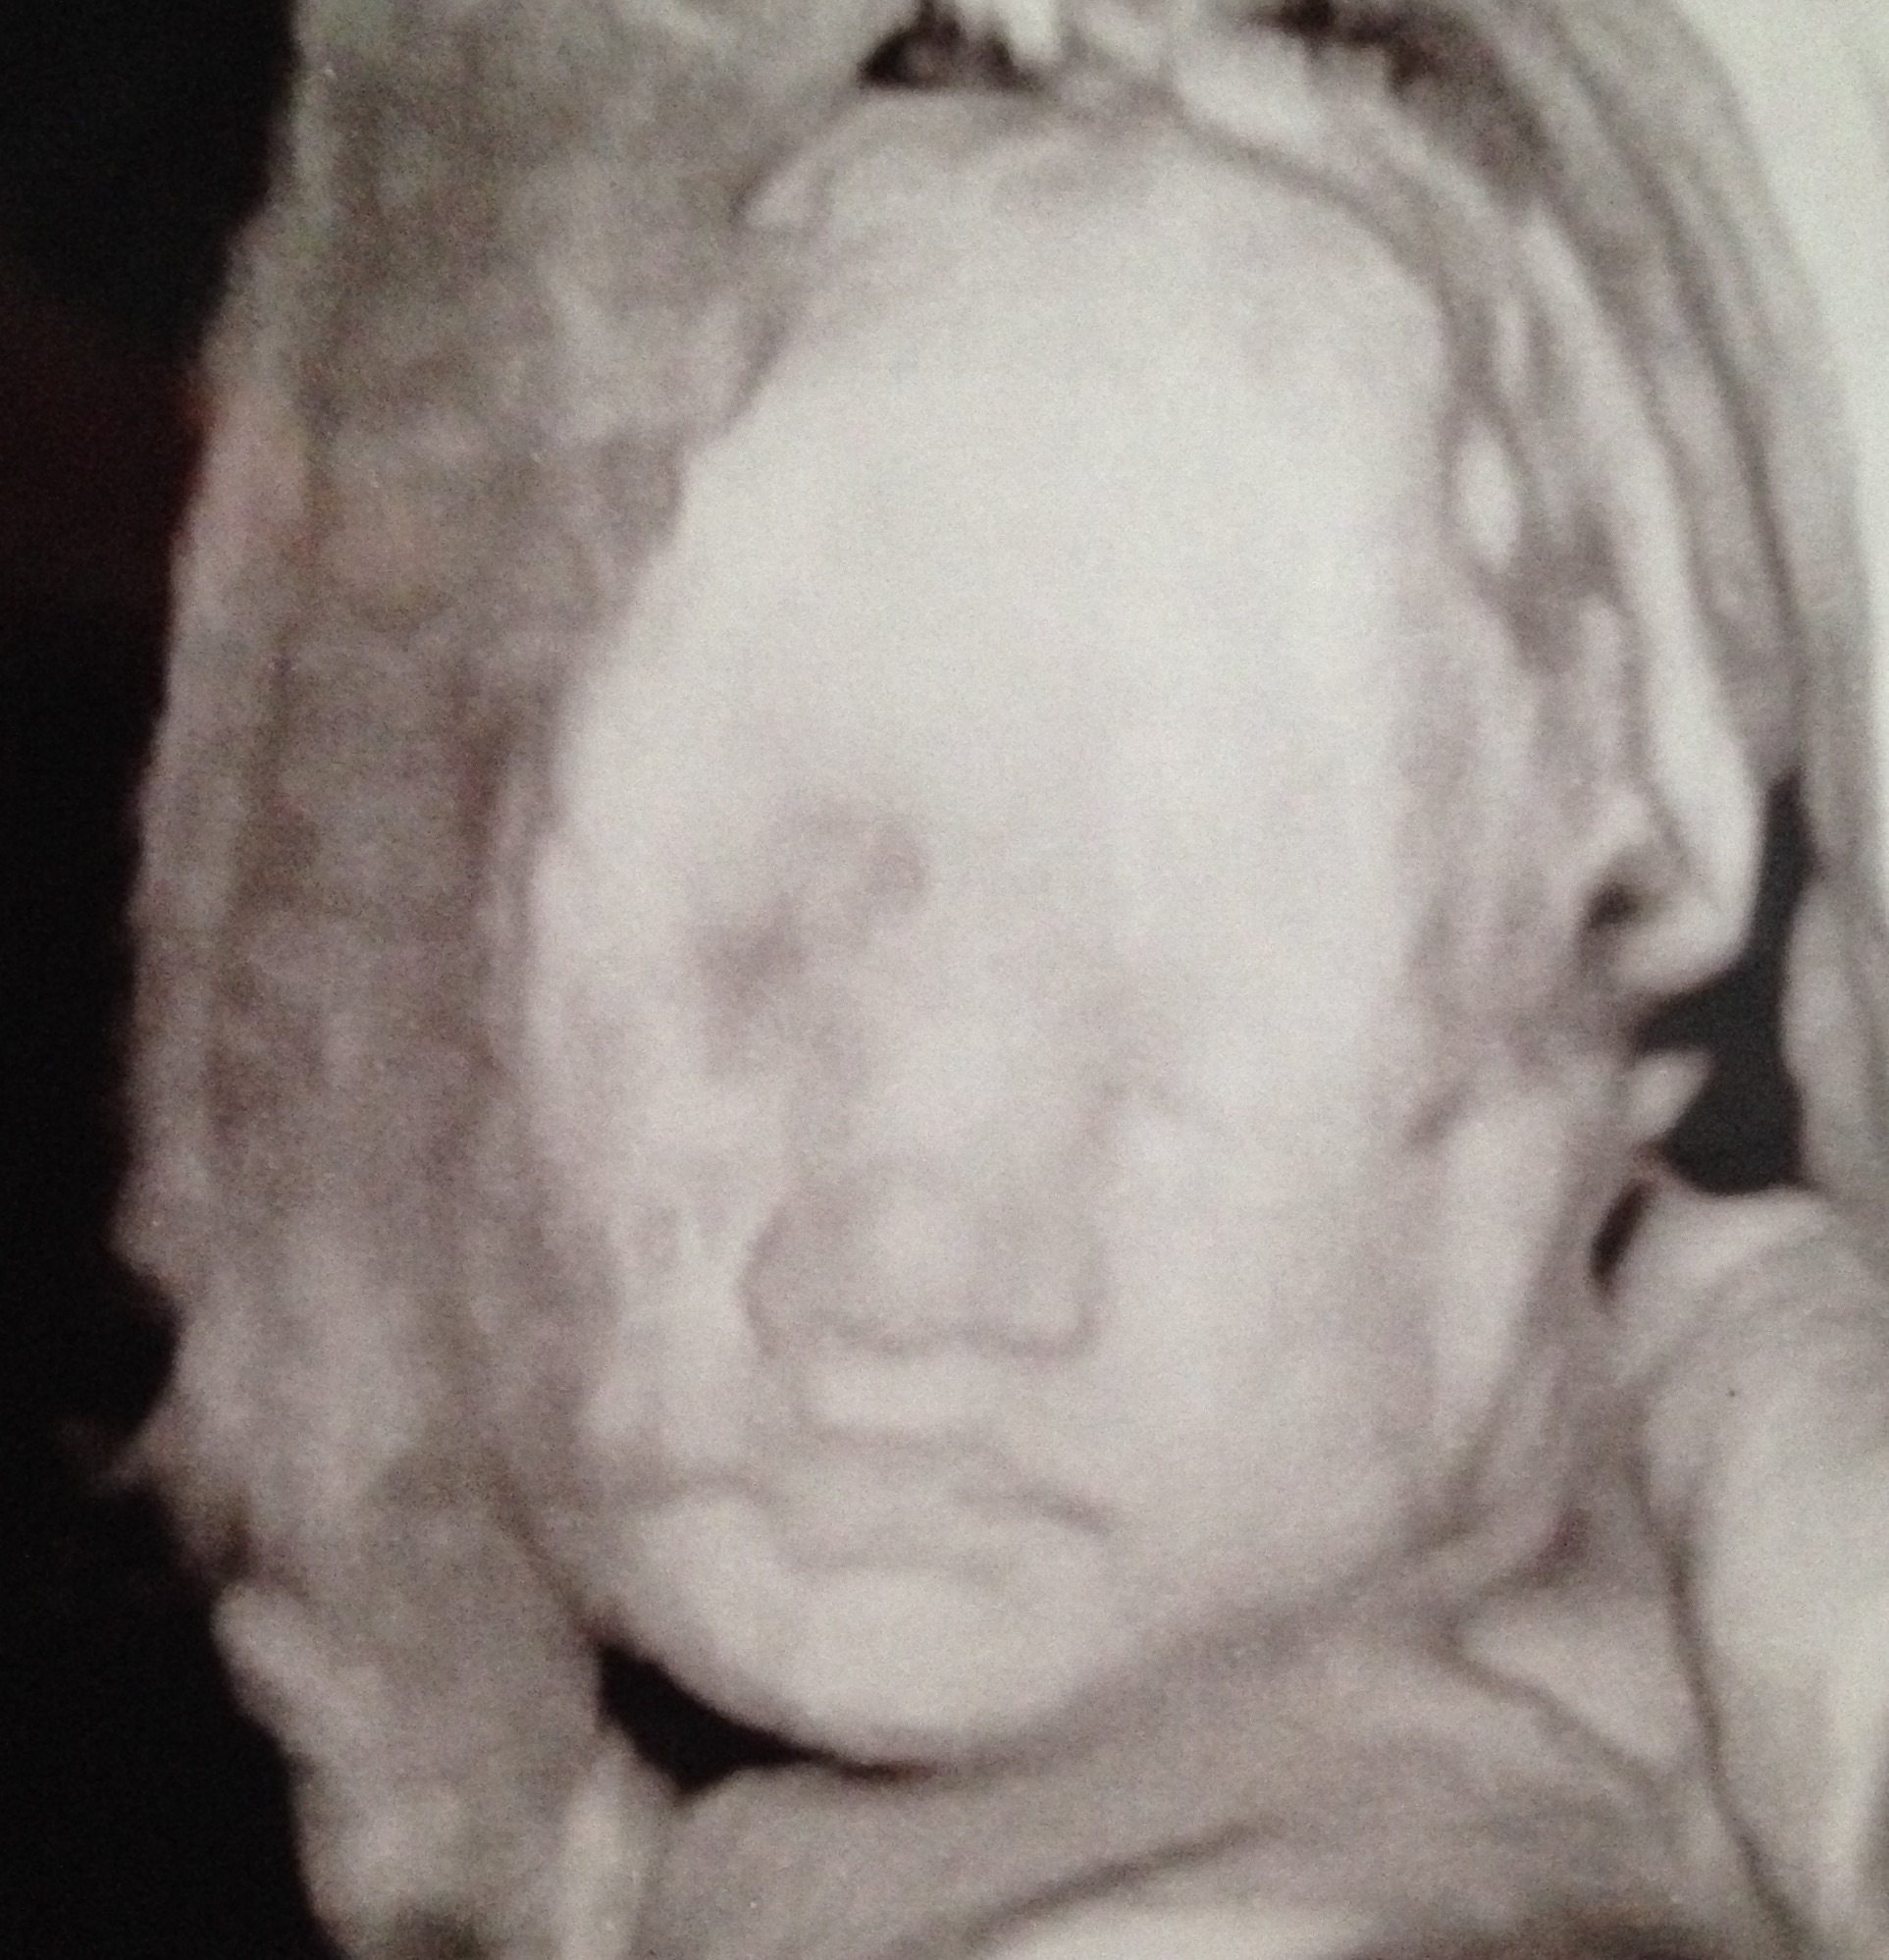

TEAM BLUE GOES HERE!